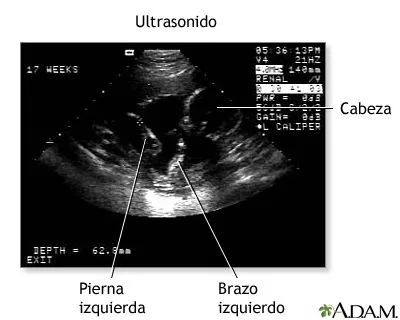

Ultrasonido bebé 3 meses

Este album de Ultrasonido bebé 3 meses con 18 fotos e imágenes no tiene descripción. Puedes sugerir una descripción de éste álbum y publicar nuevas fotos en él.

Nuestro Bebe, primer ultrasonido 2 meses gestacion.

El Ultrasonido es generalmente utilizado para: